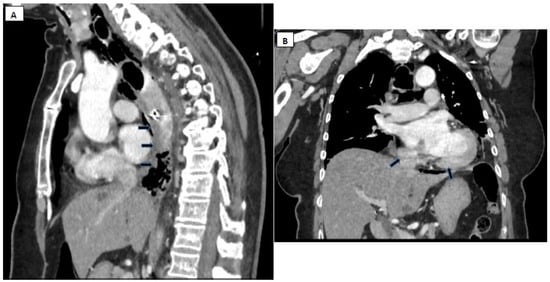

- Pneumomediastinum

- Pneumothorax (especially left-sided)

- Pleural effusion (especially left-sided)

- Localized periaortic gas

- Mediastinal fluid collections

- Thickened esophageal wall

- Gas within thoracic soft tissues, neck, or around major vessels

- Gas in the epidural space

- Pneumoperitoneum

- Gas in the retroperitoneal space

- Oral contrast extravasation from the esophageal lumen [10].